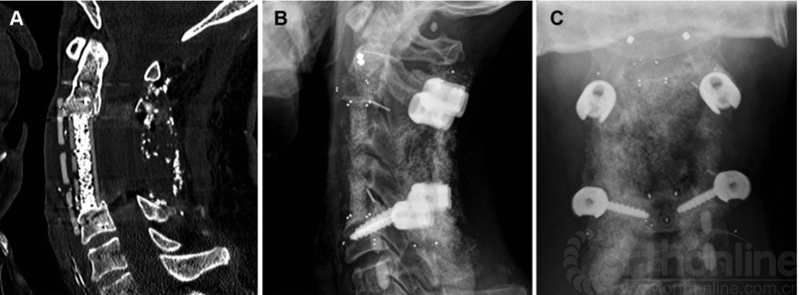

碳纤维增强PEEK(poly-ether-ether-ketone)椎弓根螺钉现在已经有制造商生产,碳纤维比例高(超过60%)(图2)。单向挤压成型的碳纤维螺钉强度独特,与标准钛螺钉相当。短的非金属碳纤维棒用于治疗脊柱转移癌的内固定系统,射线可以更好地穿透(图3)。这些系统有两个主要优点:通过减少MRI或CT成像上的伪影,更容易观察螺钉位置和监测肿瘤复发; 脊柱转移患者术后经常使放射治疗,而碳纤维结构对射线的屏蔽和散射较少,从而允许更高和更准确的放射剂量到达病灶。

图3C3和C4椎体切除术,后路C2和C5碳纤维椎弓根螺钉固定,前路置入cage和钛板。射线有效穿透可以为后续的放疗提供更准确的剂量计划。A,矢状位CT扫描显示前方碳纤维板和锁定螺钉,融合器和植骨融合。B,侧位片显示植入物的放射透明度。可以看到C2螺钉的钛多轴头和标准钛C5螺钉。所有碳纤维成分在融合器的角落用小型不透射线标志物表示,螺丝尖端、标记钛板的前端和后棒的末端。C,正位X线片。